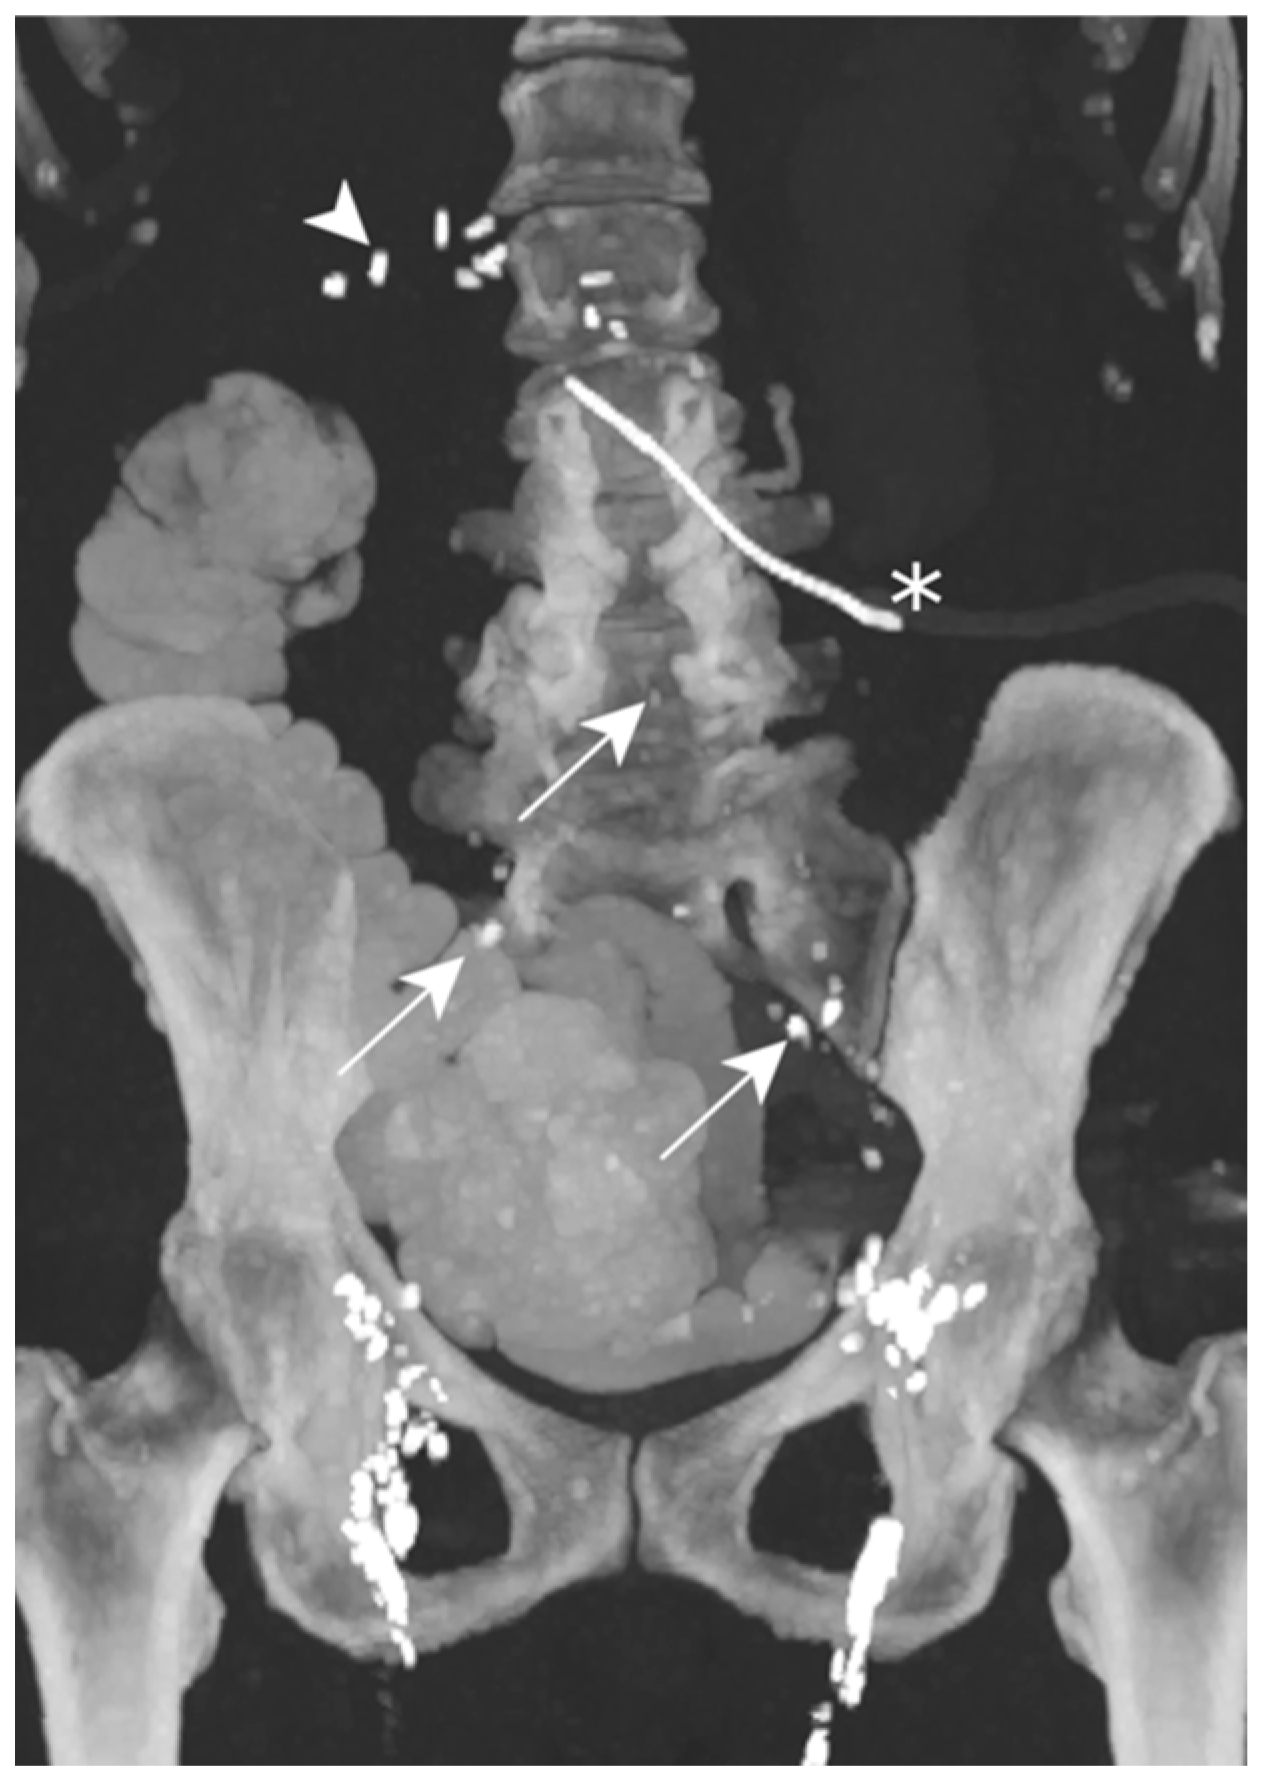

On POD 7, the abdominal post-surgical drain showed a milky substance of up to 750 mL/d. TPN was begun and, 48 h later, she underwent an LL. The images did not show the precise lymphatic leakage origin, but contrast agent was visible in the drainage catheter (Figure 9).

Figure 9.

Patient E. The maximal-intensity projection of the CT scan reconstructed in the coronal plane after a transnodal Lipiodol injection, showing contrast agent in the external and common iliac as well as retroperitoneal (white arrows) lymphatic chains. No leakage of contrast agent is visualized. The presence of radiopaque surgical material is evident in the projection of the upper right quadrant, and is related to the cephalic duodenopancreatectomy (white arrowhead). The peritoneal drainage catheter (white asterisk) is identified.

Less than 72 h after the lymphangiography, the drain output diminished to less than 60 mL/d, allowing for drain removal on POD 14.

The lymphangiography was successful in treating this post-operative chylous ascites.